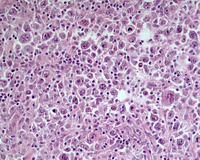

Figure 1: H&E images

HE images showing nodular architecture in many areas. Note the tumor-cell rich area in the image on the top right within the nodules.

Figure 9: Areas of transformation to DLBCL

Areas of transformation with sheets of large B-cells in the same biopsy. These are strongly positive for CD20.